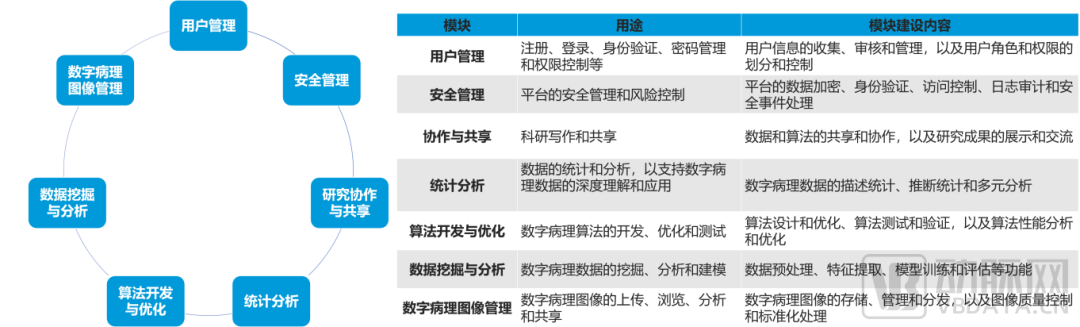

数字化病理科建设模块介绍

数字化建设模块图